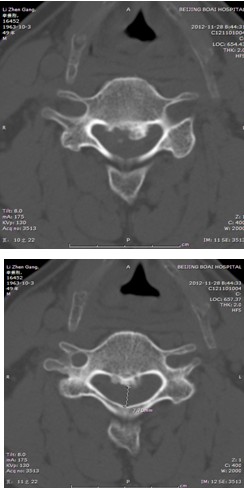

患者,男性,49岁,主因“行走不稳2个月伴右前臂麻木1个月”入院

2月前开始出现双下肢行走不稳,有踩棉花感,行走距离受限。1月前出现右侧前臂及手指麻木感。3周前诊断为“颈椎病”,保守治疗无改善,行走不稳症状加重

影像检查:

影像检查结果: